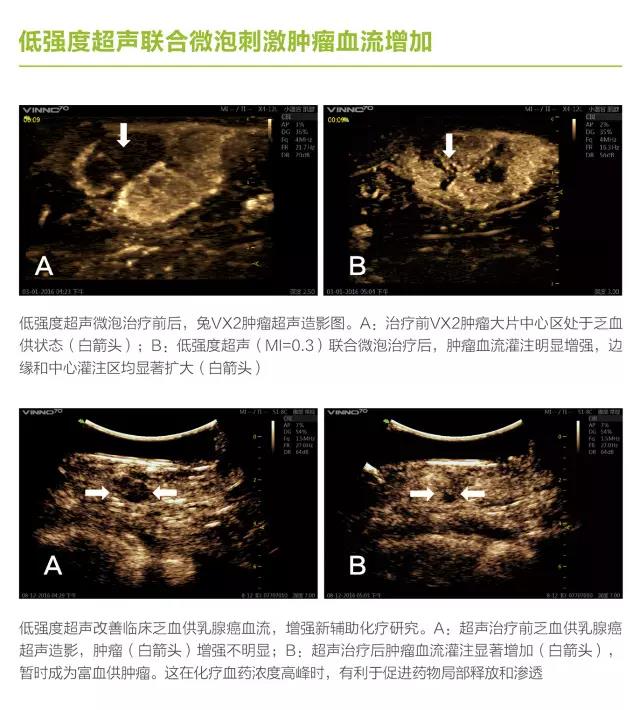

第三軍醫(yī)大學(xué)第二附屬醫(yī)院劉政教授長期從事超聲空化研究,與飛依諾公司合作推出了在診斷超聲劑量下利用超聲空化效應(yīng)完成診斷與治療新機型 VINNO70超聲診療一體機。

VINNO70 超聲診療一體機在常規(guī)超聲診斷的基礎(chǔ)上,增加了V Flash超聲空化功能,多參數(shù)可調(diào)滿足了微氣泡諧振、膨脹、內(nèi)爆等的控制